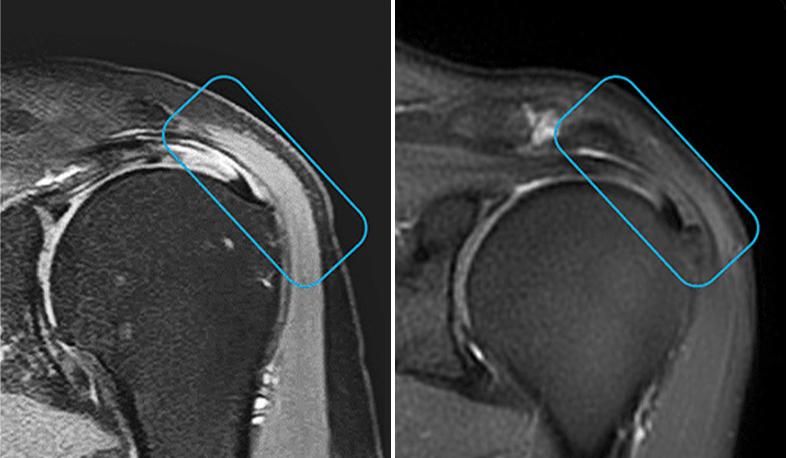

Lesiones de tendónLas CMC aplicadas por vía intratendinosa han demostrado regeneración estructural en tendón rotuliano, de Aquiles, isquiotibiales y supraespinoso, con validación mediante resonancia magnética y mejora funcional sostenida.